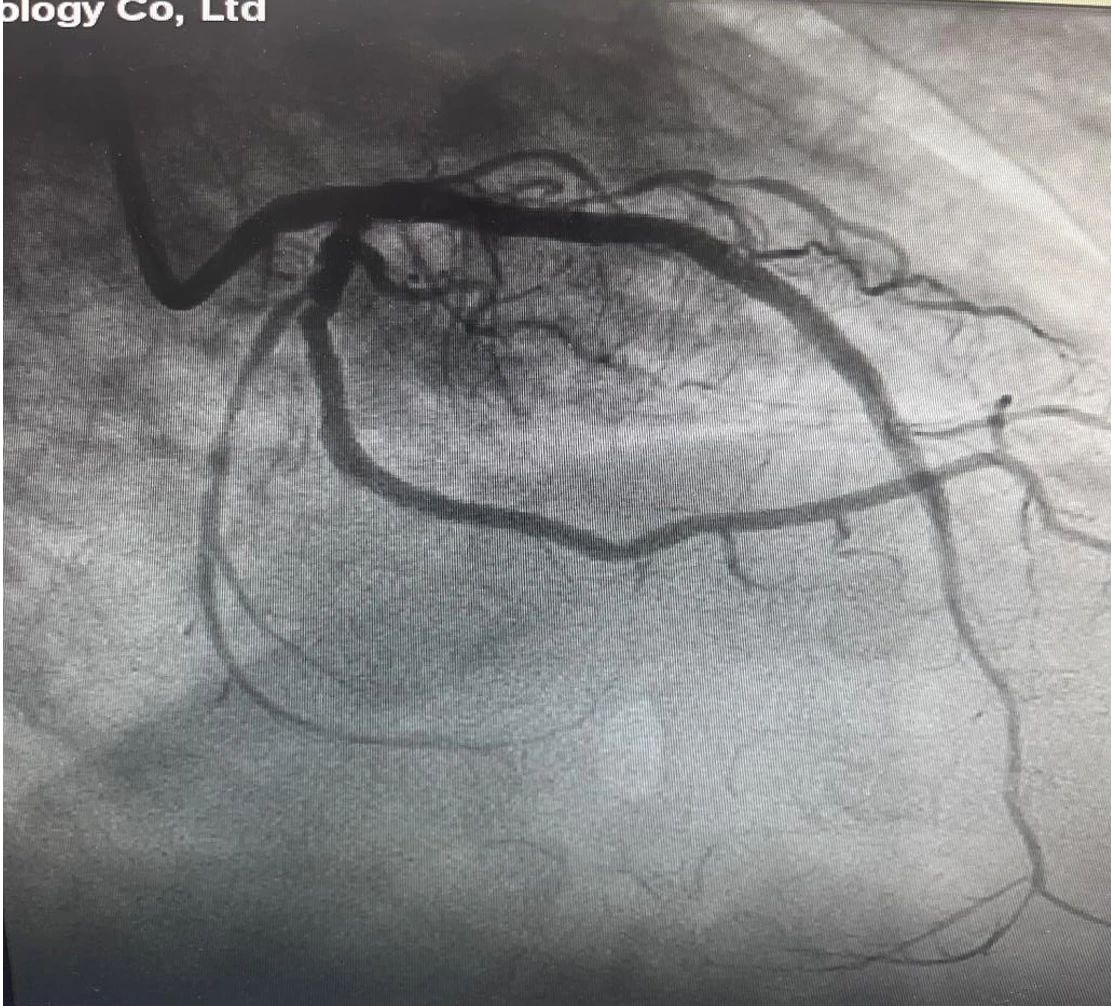

前降支旋磨及支架术后

副院长、心内二科主任索云锡带领介入团队,为刘先生实施了前降支钙化病变部位冠状动脉内膜旋磨术。经过细致的旋磨治疗,复查造影显示前降支近段、中段钙化处旋磨效果理想,之后,在前降支病变处植入支架,帮患者打通生命通道。